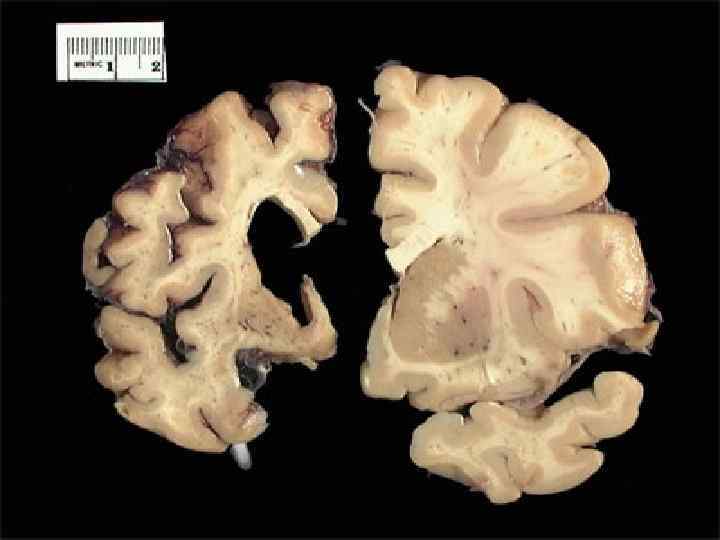

Патогенез Наблюдается прогрессирующая атрофия клеток коры головного мозга и подкорковых структур. Масса базальных ганглиев уменьшается на 50%, масса всего мозга примерно на 15— 20%. Происходит распад нервных клеток и разрастание элементов глии. Иногда обнаруживают изменения в клетках передних рогов спинного мозга. Происходят нейрохимические нарушения в головном мозге, и прежде всего изменяются процессы взаимодействия двух нейромедиаторов — гаммааминомасляной кислоты (ГАМК) и дофамина. Первично происходит дегенерация ГАМК-эргических нейронов, при этом снижается содержание тормозного медиатора ГАМК в базальных ганглиях. В этой же области головного мозга снижается и содержание декарбоксилазы глутаминовой кислоты — фермента, синтезирующего ГАМК из глутаминовой кислоты. Выпадение тормозных влияний ГАМК-системы «растормаживает» дофаминергическую систему. Такое нарушение взаимодействия ведет к повышению содержания дофамина — медиатора «движения» и возникновению хореического гиперкинеза.

Патоморфология и патофизиология Болезнь Хантингтона поражает специфические области мозга. Наиболее заметные ранние изменения затрагивают область базальных ганглиев называемую полосатым телом, которое состоит из хвостатого ядра и скорлупы. Другие повреждаемые области включают чёрную субстанцию, 3, 5 и 6 слои коры головного мозга, гиппокамп, клетки Пуркинье в мозжечке, боковые туберальные ядра гипоталамуса и часть таламуса. Базальные ганглии — часть головного мозга, наиболее заметно повреждающиеся при болезни Хантингтона — играют ключевую роль в контроле движений и поведения. Их функция полностью не ясна, но современные теории предполагают, что они являются частью когнитивной исполнительной системы и двигательного контура. Базальные ганглии в норме ингибируют большое число контуров (circuit), генерирующих специфические движения. Для инициации специфических движений кора посылает сигналы базальным ганглиям для снятия ингибирования. Повреждение базальных ганглиев может привести к снятию ингибирования или его постоянным неконтролируемым изменениям, что служит причиной затруднения начала движения или к их непроизвольной инициации, или движение может быть прервано до или после достижения желаемого результата. Накапливающиеся повреждения в этой области приводят к беспорядочным движениям, характерным для болезни Хантингтона.

А. На фронтальном срезе (МРТ, Т 1 взвешенное изображение) видно расширение боковых желудочков (отмечено стрелками) вследствие типичной для болезни Гентингтона атрофии хвостатого ядра. Б. На горизонтальном срезе (МРТ, Т 2 взвешенное изображение) видно увеличение интенсивности сигнала от скорлупы (отмечено стрелками).